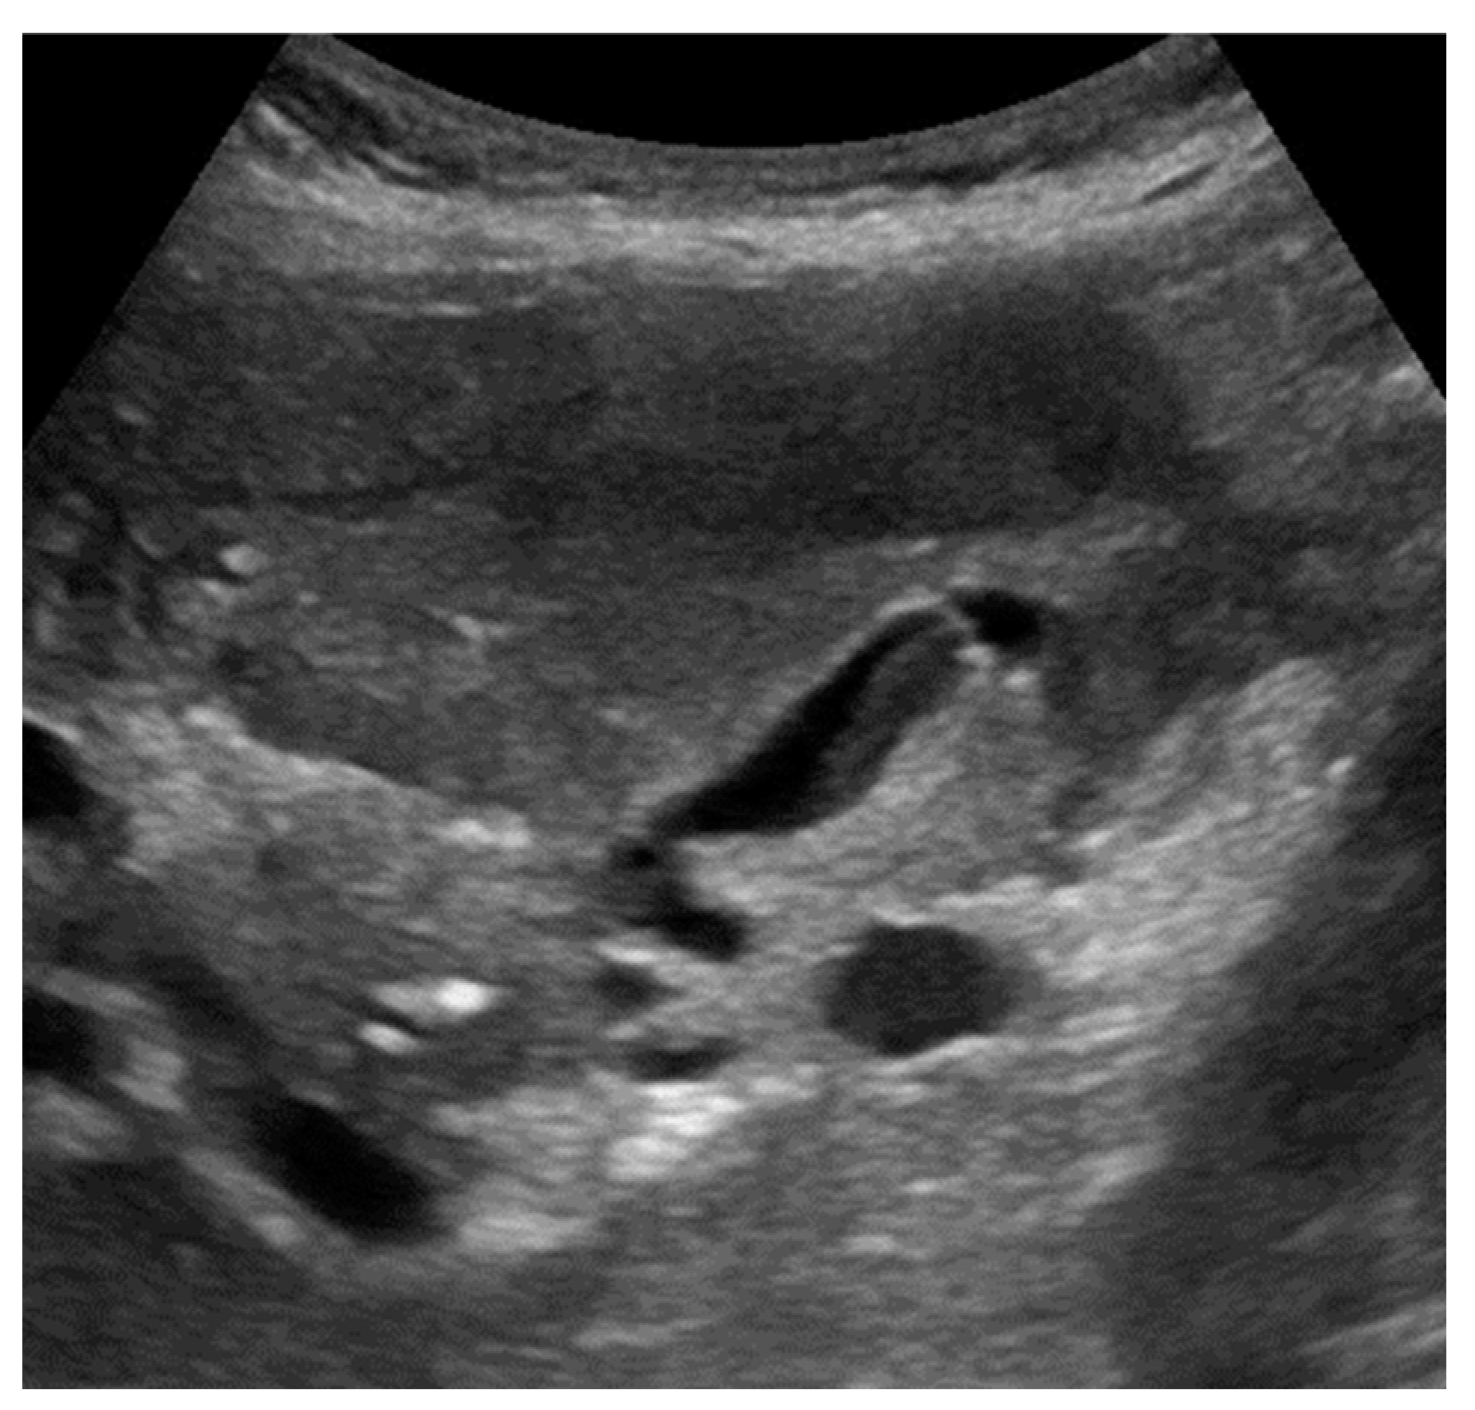

At US examination, the hallmark for the diagnosis of gallbladder perforation consists in the “hole sign”, present in 45-70% of cases [27] and characterized by a full-thickness defect of the gallbladder wall (Figure 3 and Figure 4).[44,50,57,58] Defects in the gallbladder wall are usually focal and small. However, in case of perforation secondary to infectious necrosis, a large defect may be observed. [59] The full-thickness disruption of the gallbladder wall can be further highlighted by CEUS examination. [20,37,58,60]

An indirect although specific sign of gallbladder perforation consists in the detection of gallstones outside the gallbladder lumen, typically in the peritoneal cavity. [32,44,61] Besides the above-mentioned typical features, additional signs may be found. Some authors suggest that in case of thicker gallbladder wall perforation is more frequent. [27] Pericholecystic fluid or increased fat echogenicity due to mesenteric reaction may be observed adjacent to the site of perforation. [3,32,44,62]

In case of a subacute process, gallbladder perforation generally results in pericholecystic abscess or, rarely, in a liver abscess (Figure 3).[49]